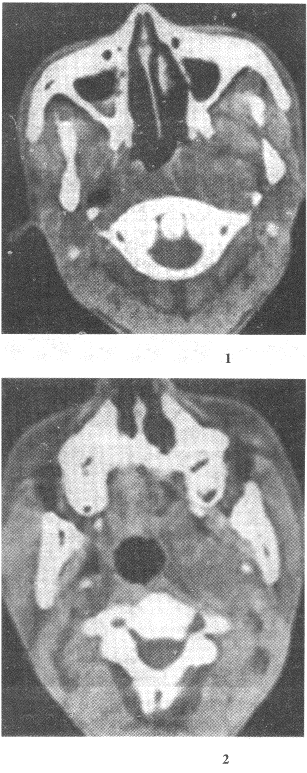

1.男性,50歲。涕中帶血絲1個月余,無發(fā)熱及咽部腫痛。CT檢查見圖所示,應(yīng)首先懷疑以下何種疾病

正確答案:A 解題思路:鼻咽癌病理上主要包括鱗狀細胞癌、腺癌、泡狀細胞癌和未分化癌。按其發(fā)展方向可分為上行型、下行型和混合型。